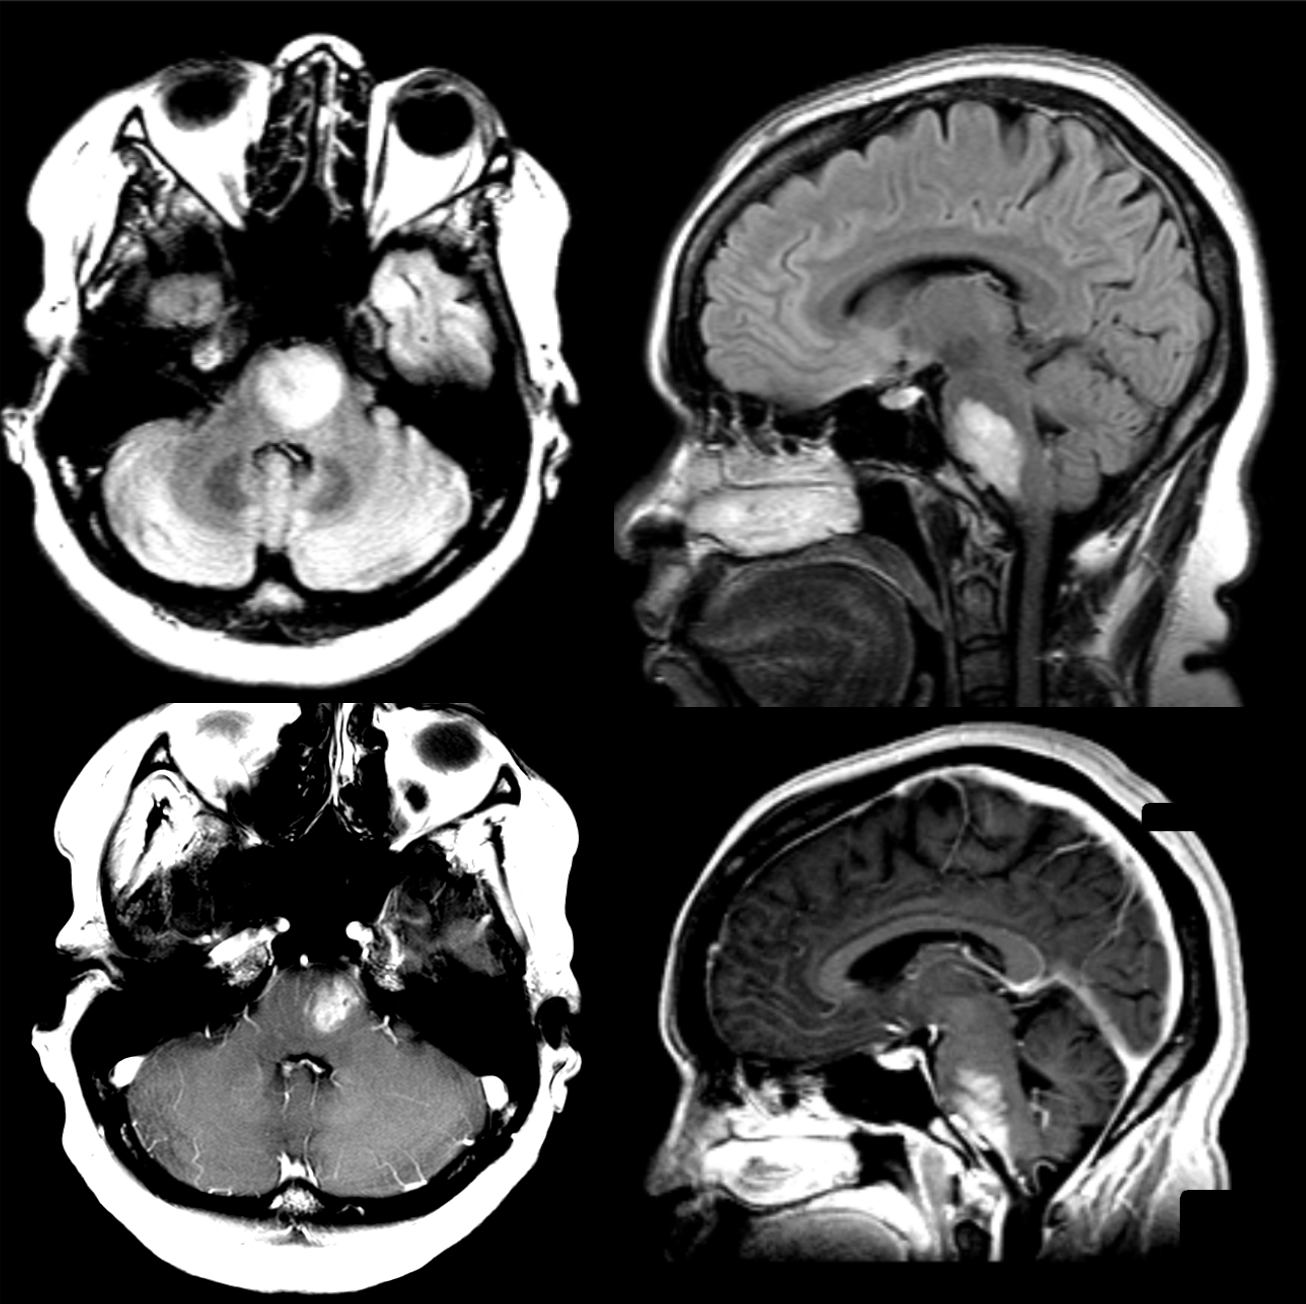

39 y/o F with right- sided weakness and left 6th nerve palsy.

Brainstem glioma